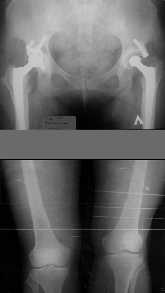

1. Иллюстрации - во вложении.

Два бедра после эндопротезирования.

Авторы операции долго думали почему больная хромает.

Сдклали снимок - одна нога короче почти на 3 см.

Здоровый человек и то будет хромать.

Согласен с мнением А.Н. Челнокова и А.А. Артемьева, что для опеределения уровня корригирующей остеотомии (остеотомий?) необходима "телерентгенограмма".

Забегая вперед (нет ответа на п.1, нет информации о состоянии функциональных и анатомо-топографических характеристик мышц бедра, степени развития рубцового процесса в коленном суставе и параартикулярных тканях) отмечу, что в аналогичных случаях (травматическая деформация дистальной трети бедра, стойкая разгибательная контрактура коленного сустава мы поступаем следующим образом:

Сначала выполняем артролиз-тенолиз-миолиз коленносго сустава и накладываем шарнирный чрескостный аппарат для пассивно-активной разработки движений в коленном суставе. Компоновка аппарата должна предусматривать возможность фиксаци фрагментов после корригирующей остеотомии. Затем устраняем деформацию бедра (корригирующая остеотомия).

Операция может быть разбита на 2 этапа: восстановление движений в коленном суставе - корригирующая остеотомия. Это, к сожалению, "в общем и целом".